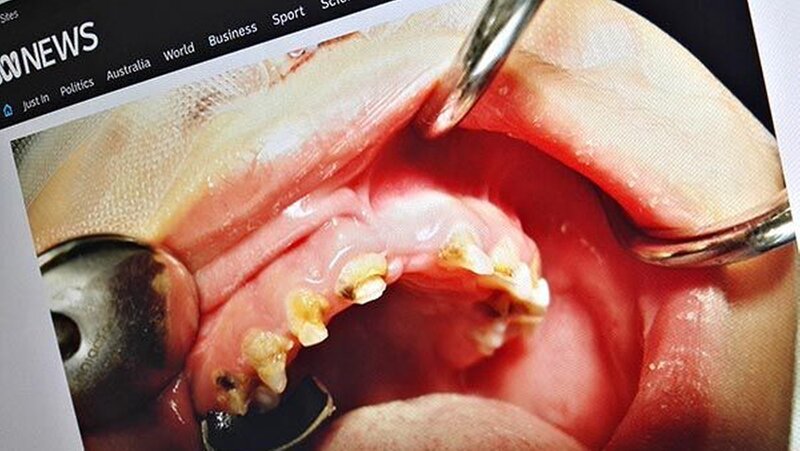

Australien: ECC nimmt deutlich zu

Zahnarzt Dr. Mark Penrose vom South Australien Dental Service, bezeichnete die Lage gegenüber

ABC News

als alarmierend und frustrierend, angesicht der Tatsache, dass die Fälle einzig auf stark zuckerhaltige Nahrung und mangelnde Mundhygiene zurückzuführen seien.

Es sei nicht ungewöhnlich, bis zu 12 oder 14 Zähne bei Kindern extrahieren zu müssen, die gerade einmal drei oder vier Jahre alt sind, berichtet auch Dr. Sophie Beaumont vom Royal Dental Hospital in Melbourne.